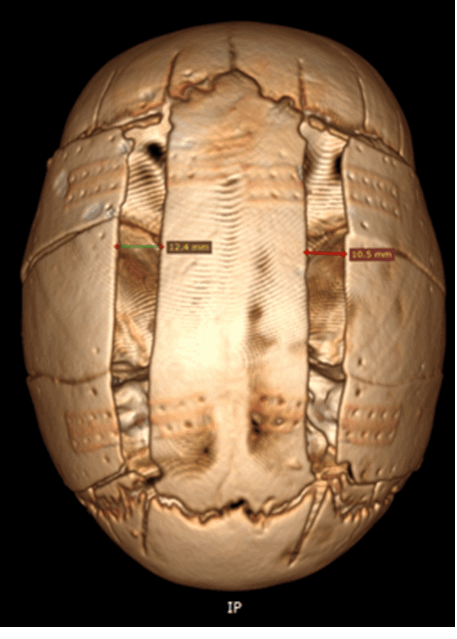

Оксицефалия в результате преждевременного сращения венечного и сагиттального швов.

д) Диагностика. Рентгенологические признаки краниосиностозов (Avivet al., 2004) включают заметное усиление пальцевых вдавлений, особенно выраженных при сращении нескольких швов (рис. 5.5). При сагиттальном краниосиностозе обычно отмечается двустороннее преобладание пальцевых вдавлений в области лба. Бороздки от венозных синусов глубокие и хорошо видны. Возможное выраженное увеличение и эрозии спинки турецкого седла. Описанные признаки, которые в некоторых случаях могут выявляться при бессимптомном течении заболевания, свидетельствуют о длительном повышении ВЧД, подтверждаемым непосредственным измерением. Швы не видны, а в области их нормального расположения отмечается гиперостоз.

Кости свода черепа тонкие с заметными пальцевыми вдавлениями. Венозные синусы глубоко проникают в кость (7-летний мальчик с внутричерепной гипертензией и отеком диска зрительного нерва.